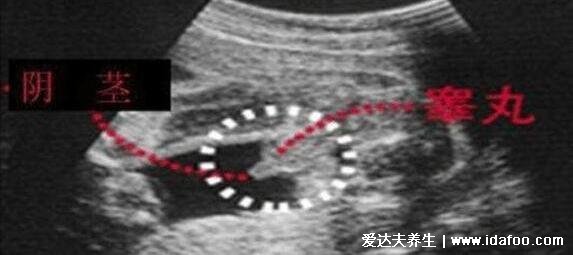

怀孕三个月之后,胎儿的性别特征已经明显形成了,通过四维彩超可以观察到胎儿下半身的性别特征。怀男孩的单子上可以看到3个亮点,胎儿两腿中间有小突起,像菌状的物体,是男性生殖器的形状。不过一般医院规定检查会避开宝宝生殖器......